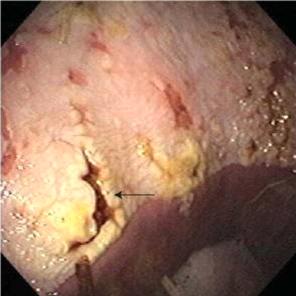

Активные язвы обычно бывают у жеребят в возрасте около 9 месяцев и моложе. Обычно они поражают нежелезистую зону слизистой вдоль большой или малой кривизны возле складчатого края или в железистой зоне. Клинические признаки проявляются в том случае, если латентные язвы у жеребят увеличиваются в размерах, приобретают более выраженный диффузный характер, сливаются. В тяжелых случаях такие поражения могут кровоточить (рис.21, с.32). Наиболее частыми симптомами являются диарея, потеря аппетита, отставание в росте, взъерошенность шерстного покрова, увеличенный живот, скрежетание зубами, дорсальное лежачее положение, гиперсаливация, прерывистое сосание, колики. При более обширных язвах наблюдается боль при пальпации абдоминальной области от мечевидного отростка в каудальном направлении. Колики носят более тяжелый характер, жеребята катаются по земле или лежат в дорсальном положении. Эти признаки возникают вследствие гастро-эзофагального рефлюкса и растяжения желудка. [6, 11, 15]

Поражения двенадцатиперстной кишки (рис.2) встречаются реже, чем поражения желудка (примерно у 5% жеребят). Дуоденальные язвы трудно диагностировать при жизни, так как основными клиническими признаками являются абдоминальный дискомфорт и угнетенность. У жеребят, имеющих "классические" признаки гастродуоденальных язв, такие как бруксизм и птиализм, часто находят поражения двенадцатиперстной кишки.